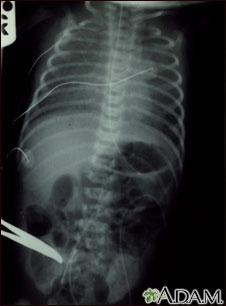

Retorno venoso pulmonar total anómalo, rayos X

El retorno venoso pulmonar totalmente anómalo es una forma de enfermedad cardíaca congénita.